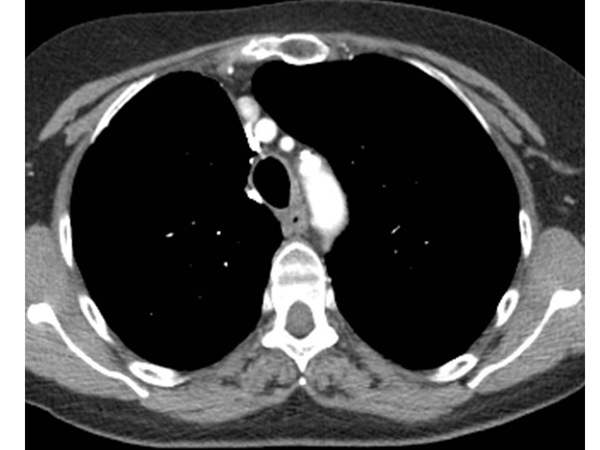

При обращении в клинику пациент направляется на комплексное обследование, которое включает: